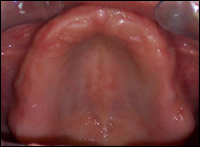

Fig 4 & 5: Pre-operative view of the edentulous maxilla. A 12-unit porcelain bridge was cemented in place.